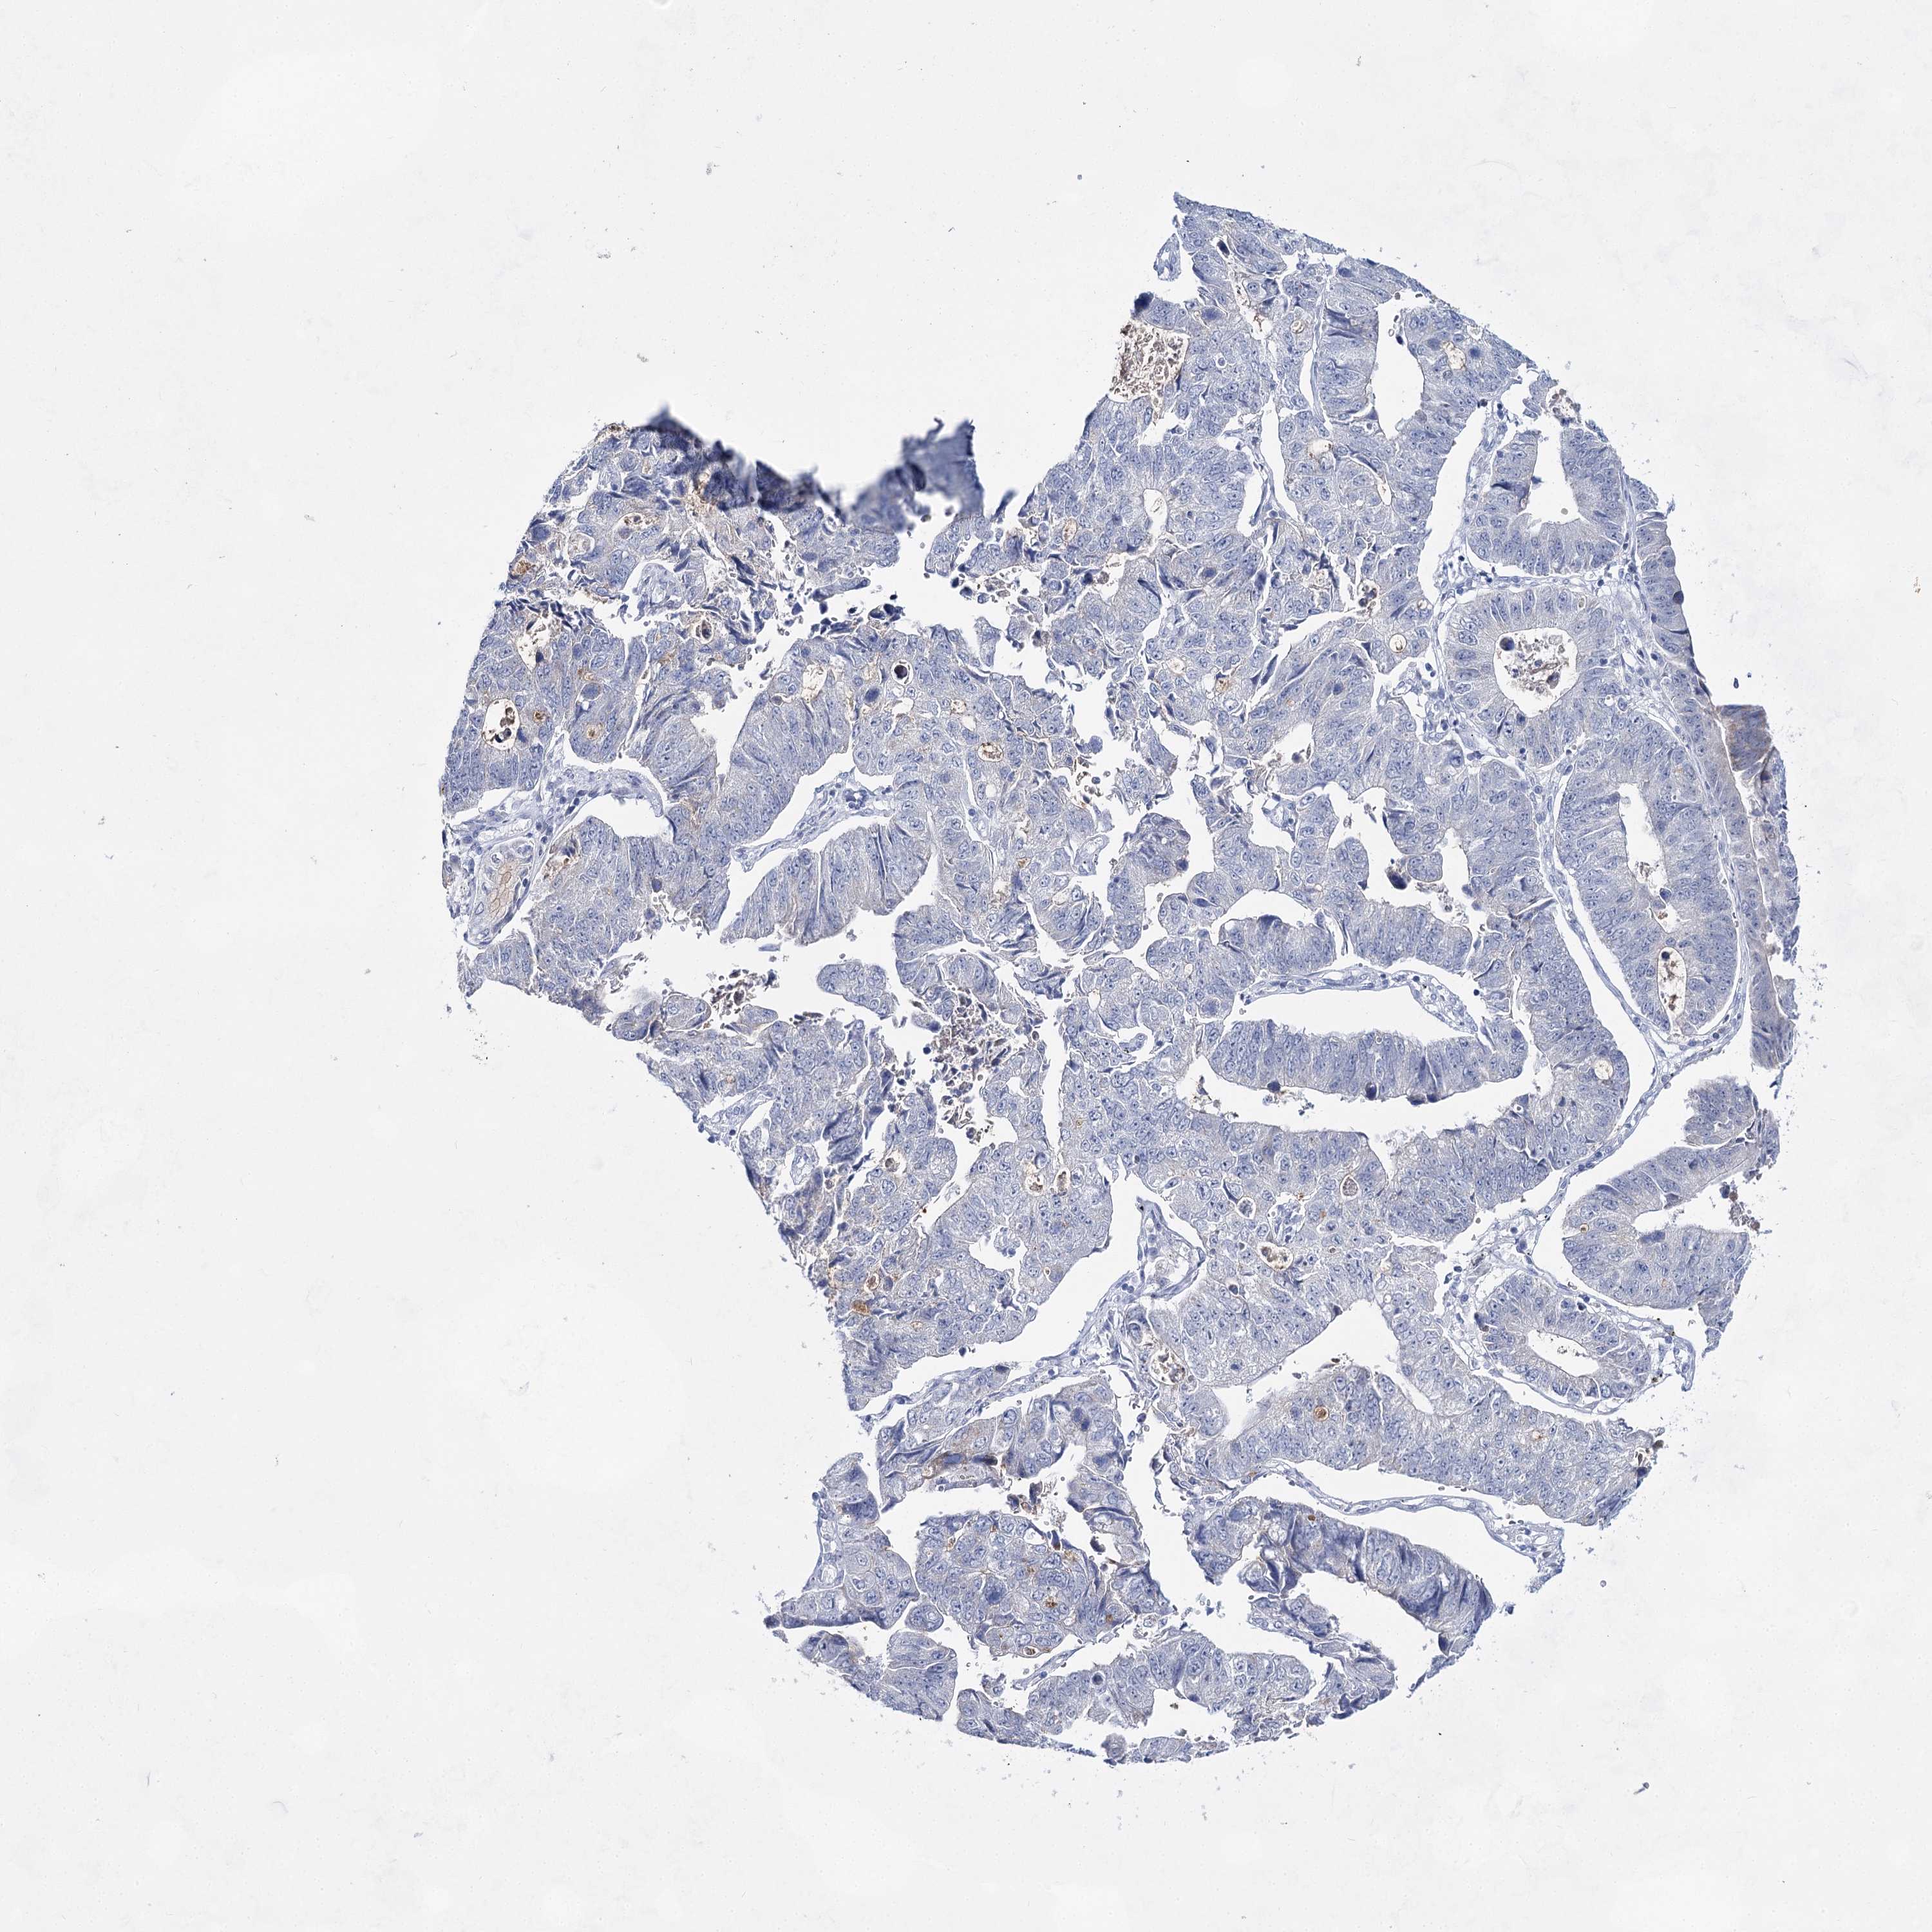

STOMACH CANCER - Protein expressioni

A mouse-over function shows sample information and annotation data. Click on an image to view it in a full screen mode. Samples can be filtered based on level of antibody staining by selecting one or several of the following categories: high, medium, low and not detected. The assay and annotation is described here.

Note that samples used for immunohistochemistry by the Human Protein Atlas do not correspond to samples in the TCGA dataset.

Antibody stainingi

Antibody staining in the annotated cell types in the current human tissue is reported as not detected, low, medium, or high, based on conventional immunohistochemistry profiling in selected tissues. This score is based on the combination of the staining intensity and fraction of stained cells.

Each image is clickable and will lead to virtual microscopy that enables deeper exploration of all samples and also displays staining intensity scores, fraction scores and subcellular localization as well as patient and tissue information for each sample.

Antibody HPA036752

Antibody HPA036753

Adenocarcinoma, NOS